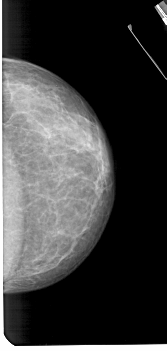

A_1419_1.RIGHT_CC

RIGHT_CC LINES 5251 PIXELS_PER_LINE 2491 BITS_PER_PIXEL 12 RESOLUTION 43.5 NON_OVERLAY